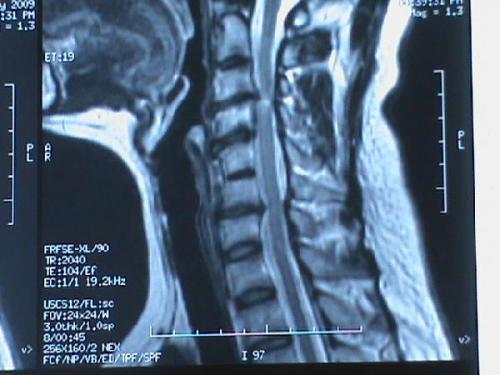

哪些人不能做颈椎牵引?

5.脊髓明显压迫者;